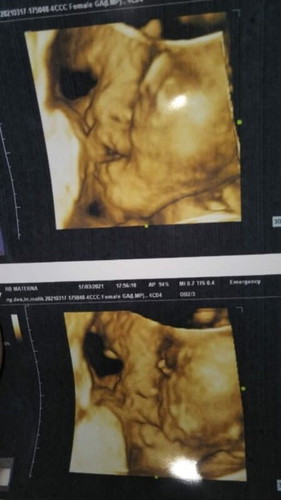

Kemarin saya USG usia kehamilan 27 week,alhmdulillah kepala sudah dibawah,BB janin 1353gr,apa normal usia kandungan sm BB janin nya? Tapi perut saya masih kecil bgt ,apa krna badan awal saya juga kecil yah?kata bidan sih bb janin gaush gede2 toh ibunya juga ga gede,lahiran kecil aja sewaktu sudh melahirkan bayi baru gemuk,drpd di gedein bb janin nya pas lahiran mlah kurusan,apa benar? #seriusnanya #bantusharing #ingintahu #firstbaby